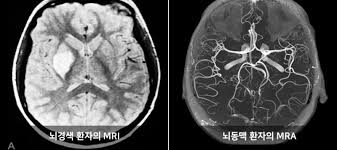

MRA는 MRI 기술을 기반으로 하며, **혈관만을 대상으로 하는 특수 영상검사**입니다. MRI는 인체 내부 **연부조직, 장기, 뼈, 근육, 신경** 구조를 정밀하게 촬영하는 데 유용합니다. 아래에서 두 검사의 정의, 원리, 장단점, 비용·보험, 추천 상황 등을 자세히 비교해 드립니다.

- MRI (자기공명영상): 강한 자기장과 라디오파를 사용해 내부 구조(근육, 뇌, 장기 등)의 단면 영상을 생성합니다. 방사선 노출 없이 해상도가 뛰어나 종양, 염증, 디스크 병변 진단에 탁월합니다 :contentReference[oaicite:1]{index=1}.

- MRA (자기공명혈관조영술): MRI 원리를 적용해 **혈관 내부 구조와 혈류 흐름**을 3D 영상으로 확인하는 검사입니다. 동맥류, 혈관 협착·폐쇄·혈전 등의 진단에 사용됩니다 :contentReference[oaicite:2]{index=2}.

즉, MRI는 **조직 중심** 진단, MRA는 **혈관 상태와 혈류 흐름**을 중점으로 합니다 :contentReference[oaicite:3]{index=3}.